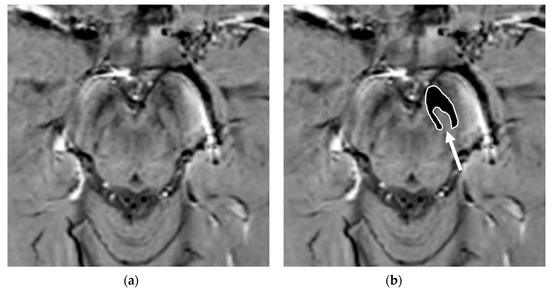

4.2. Nigrosome-1 Imaging